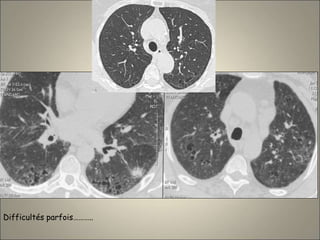

Association d’ECL et

d’EPS

Association d’EPL et

d’ECL

Difficultés parfois………..